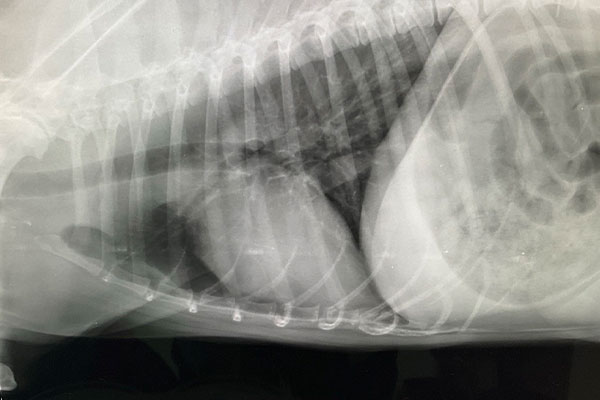

レントゲン検査で「異物の疑い」

まずはレントゲン検査を実施。撮影した画像は、レントゲン診断を得意とする獣医師にも確認してもらいました。

その結果、食道内異物が疑われる状態と判断されました。

外からは見えず、症状も咳のみ。だからこそ、慎重な判断が必要なケースでした。